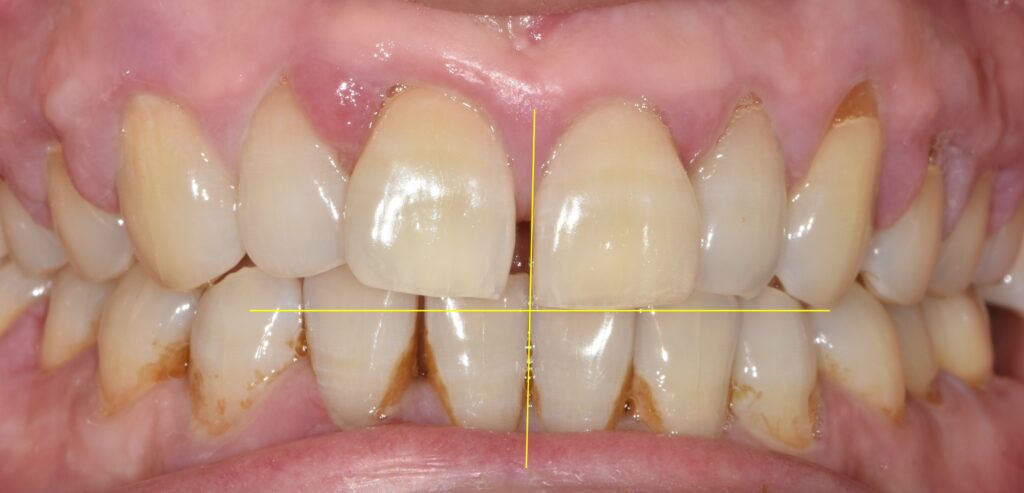

남성분의 입안 상태는 위와 같습니다.

사진을 보시면 대문니 오른쪽 대문니가(사진상으로는 왼쪽) 틀어져 있는 것을 볼 수가 있었습니다.

사실 레진을 이용하여 앞니를 수복하는 치료는 그리 어렵지 않습니다.

다만 치아의 축이 위처럼 틀어져 있는 경우는 다소 어려울 수 있습니다.

레진으로 어떻게 심미적으로 잘 치료할지 계획을 하고 치료를 진행했습니다.